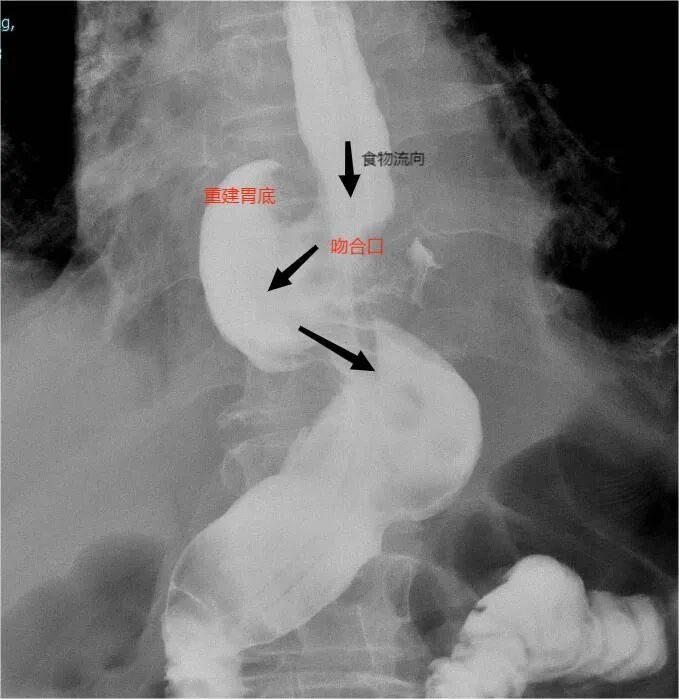

关键手术步骤(如下图):

2.术中胃镜定位肿瘤边界,肿瘤切除范围达到根治要求、保留部分胃功能;手术安全性高,术后营养状况良好。

3.符合人体生理解剖的消化道重建方式,术后不易发生反流性食管炎、吻合口狭窄等并发症。